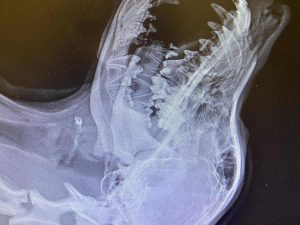

Shortly after the first public post about the Blue Heeler, she was struck by a car. Her jaw was broken, and her leg was dislocated. Thankfully, she was rushed to Priority Pet Care in West Plains, where Dr. Wes Gunter and his team immediately began emergency care.

The team acted quickly, performing emergency surgery to repair her jaw and leg. She pulled through.